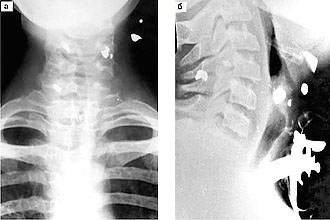

Для диагностики используется рентгенография, на которой выявляются признаки мелкоочаговой пневмонии. При пальпации живота может быть обнаружена спленомегалия. Ларингоскопия показывает глубокие болезненные язвы, затрудняющие глотание. Подтверждение диагноза осуществляется на основе серологических, микроскопических и бактериологических исследований.

Диагностика травм гортани осуществляется на основе рентгенологических и ларингоскопических исследований, ультразвукового обследования и компьютерной томографии.